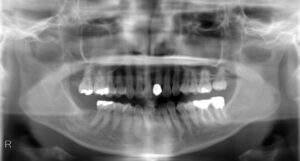

上下7本欠損症例

BEFORE AFTER 38歳男性/上下7本欠損/インプラント埋込手術 【治療内容】 むし歯の治療希望でご来院された患…